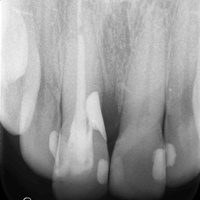

Wybielanie obejmujące pojedyncze zęby jest dość często spotykane. Najczęstszą przyczyną dyskoloracji zęba jest obumarcie miazgi i brak następowego poprawnego leczenia kanałowego, lub leczenie nieprawidłowe. Czasami udaje się przeprowadzić proces wybielania, który jest zadowalający dla pacjenta, a czasami w oparciu o uzyskany wynik można przeprowadzić leczenie protetyczne np. koroną lub licówką całoceramiczną.

Trzeba jednak uważać, ponieważ nieumiejętnie przeprowadzone wybielanie może być przyczyną resorpcji wewnętrznej i może sie skończyć utratą całego zęba...juz wybielonego. Poniżej zdjęcia przed i po leczeniu mikrochirurgicznym resorpcji.